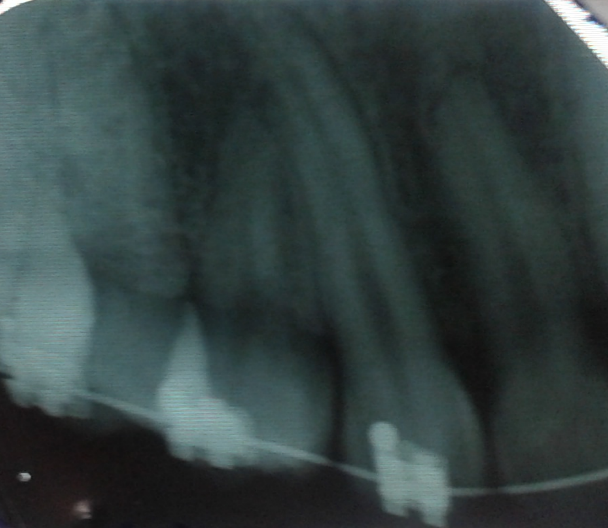

*DESCRIPCIÓN DE LA PLACA RADIOGRAFICA DEL INCISIVO CENTRAL

SUPERIOR: Una placa Peri apical

-No presenta una tapadura dentaria

-Presenta buen revelado

-sus pieza dentaria 21 superpuestas izq. el incisivo descendió perfectamente ocupando los dos espacios de los incisivos.

Por la ausencia de la pieza dentaria 11 superior Der.

La cual se encuentra actualmente alojada en el maxilar superior en sentido distal mesial, (de adentro hacia afuera). La cual podemos observar en la placas realizadas.